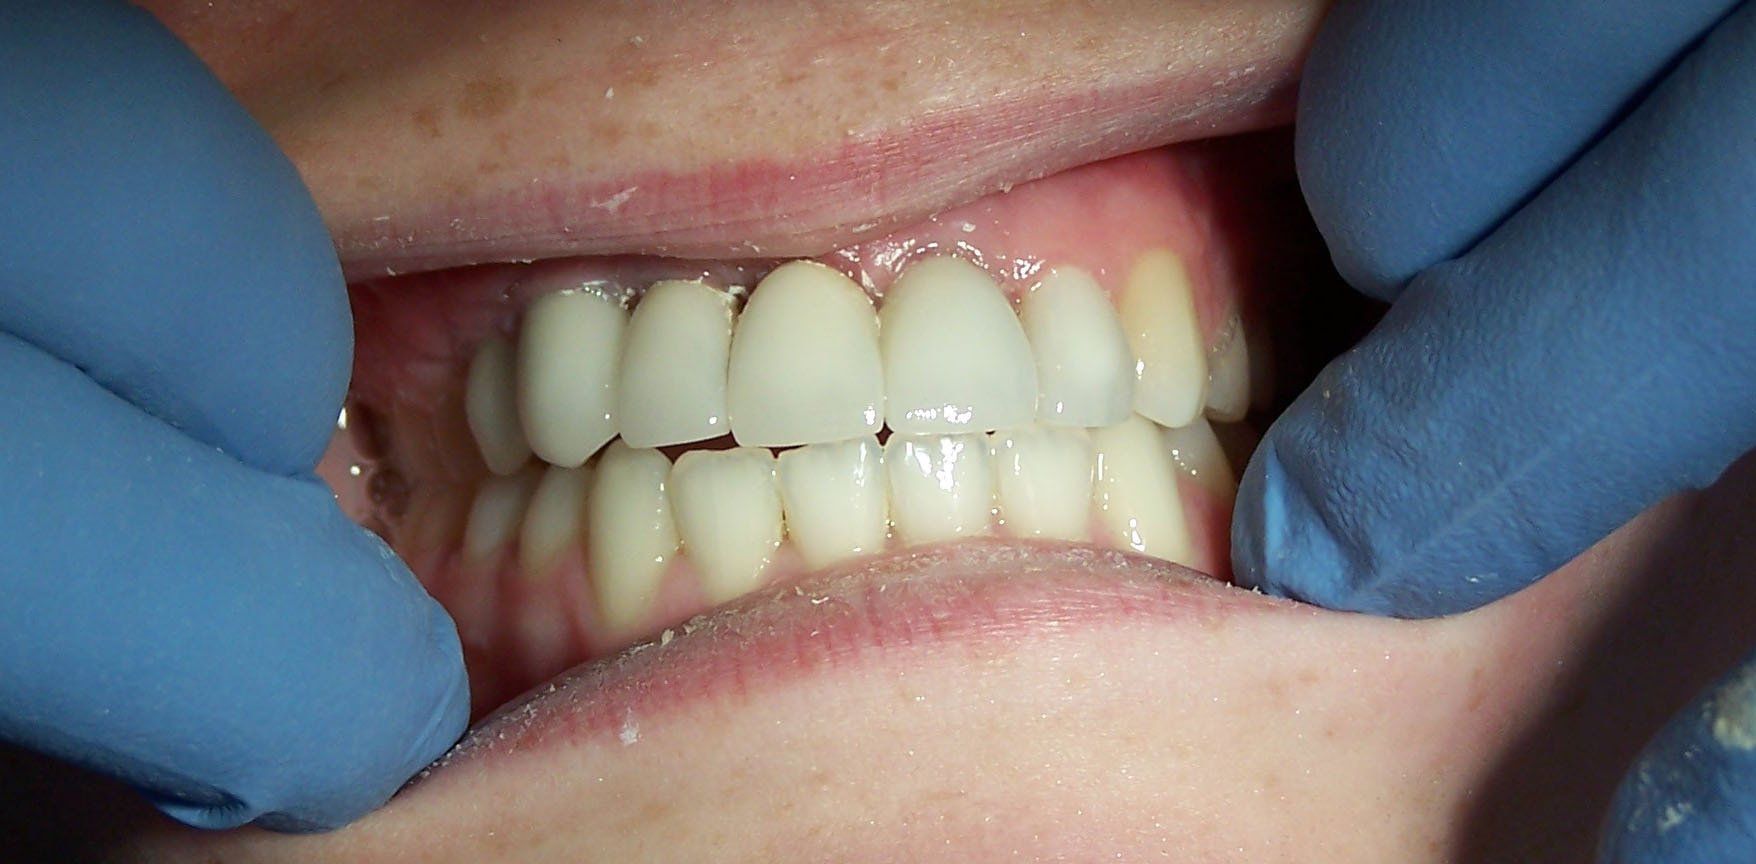

Ally After

Button